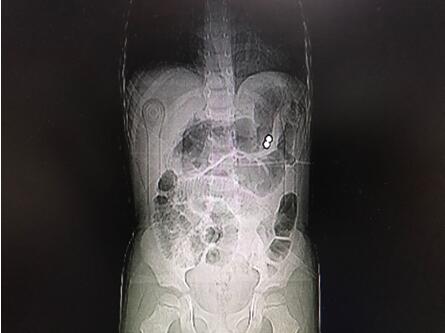

通訊員唐水平報道:近日,市中心醫(yī)院華新普外科收治了一位4歲的腹痛患兒,進院后檢查發(fā)現(xiàn)腹腔內有金屬異物及膈下游離氣體、腹腔積液,診斷為消化道穿孔并彌漫性腹膜炎。

經手術探查發(fā)現(xiàn)胃體近大彎側、曲式韌帶下方8cm處空腸及橫結腸系膜各有一0.5cm大小穿孔,在胃穿孔處的胃腔內外各發(fā)現(xiàn)一彩色磁力珠。經修補胃腸道穿孔及抗感染、補液治療,患兒術后順利康復院。